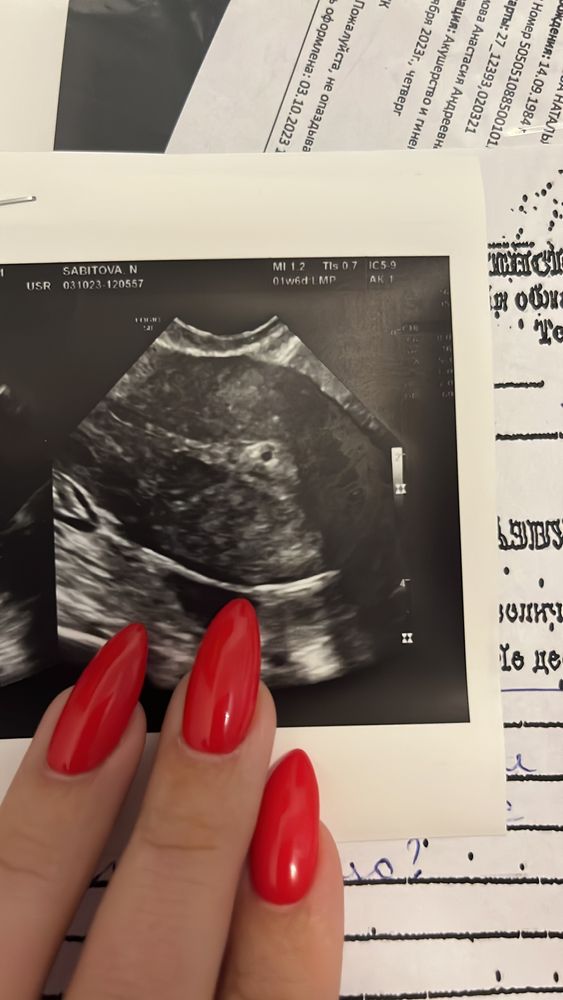

Плодное яйцо или киста?

Анализы и процедуры. Помощь в расшифровке результатовДевчонки привет, должны пойти в программу эко вчера,сделали узи 20д.ц,а там черное пятнышко похожее на плодное яйцо врач ре сразу воскликнула Плодное яйцо..,врач узи тоже говорит :"Очень похоже,да" крутили вертели и пришли к выводу что это пя, вышла из кабинета узи в процедурный сдала кровь на хгч в процедурке мед сестра говорит какое плодное яйцо на 20д.ц? Я говорю и у меня не сходится. Девчонки, врачи у меня хорошие я им доверяю, рассказывали мне какие у них были чудеса. В прошлом месяце овуляции не было,тогда надежда на этот цикл.., но..., я приезжала на prp процедуру и врач смотрела меня на узи овуляция не собиралась наступать,врач сказала сходить на фолликулометрию на 16ый д.ц. Настал 16 д.ц пошла на фоллик.метрию сказали что овуляция прошла на 14ый день и оч плохая,какая Як вышла не известно да и эндометрий 5мм беременности некуда цепляться. И вот вчера на 20д.ц плодное яйцо нашли, я полезла в интернет в общем аденомиоз может выглядеть как чёрная точка и по фото в интернете похоже на плодное яйцо. Вобщем врач сказала либо пя ,либо киста эндометрия,ждем хгч. Я сидела вчера в клинике меня всю трясло, мозг понимает что это не может быть беременностью,а сердце разрывалось хотелось верить в чудо,но так страшно еще раз разочароваться. У кого такое было девчонки? Хгч только завтра придёт,я уже ночь не спала,ненормальная, не могу себя успокоить. Живот болит на месячные,грудь не болит. Видимо судьба решила с играть со мной злую шутку😔